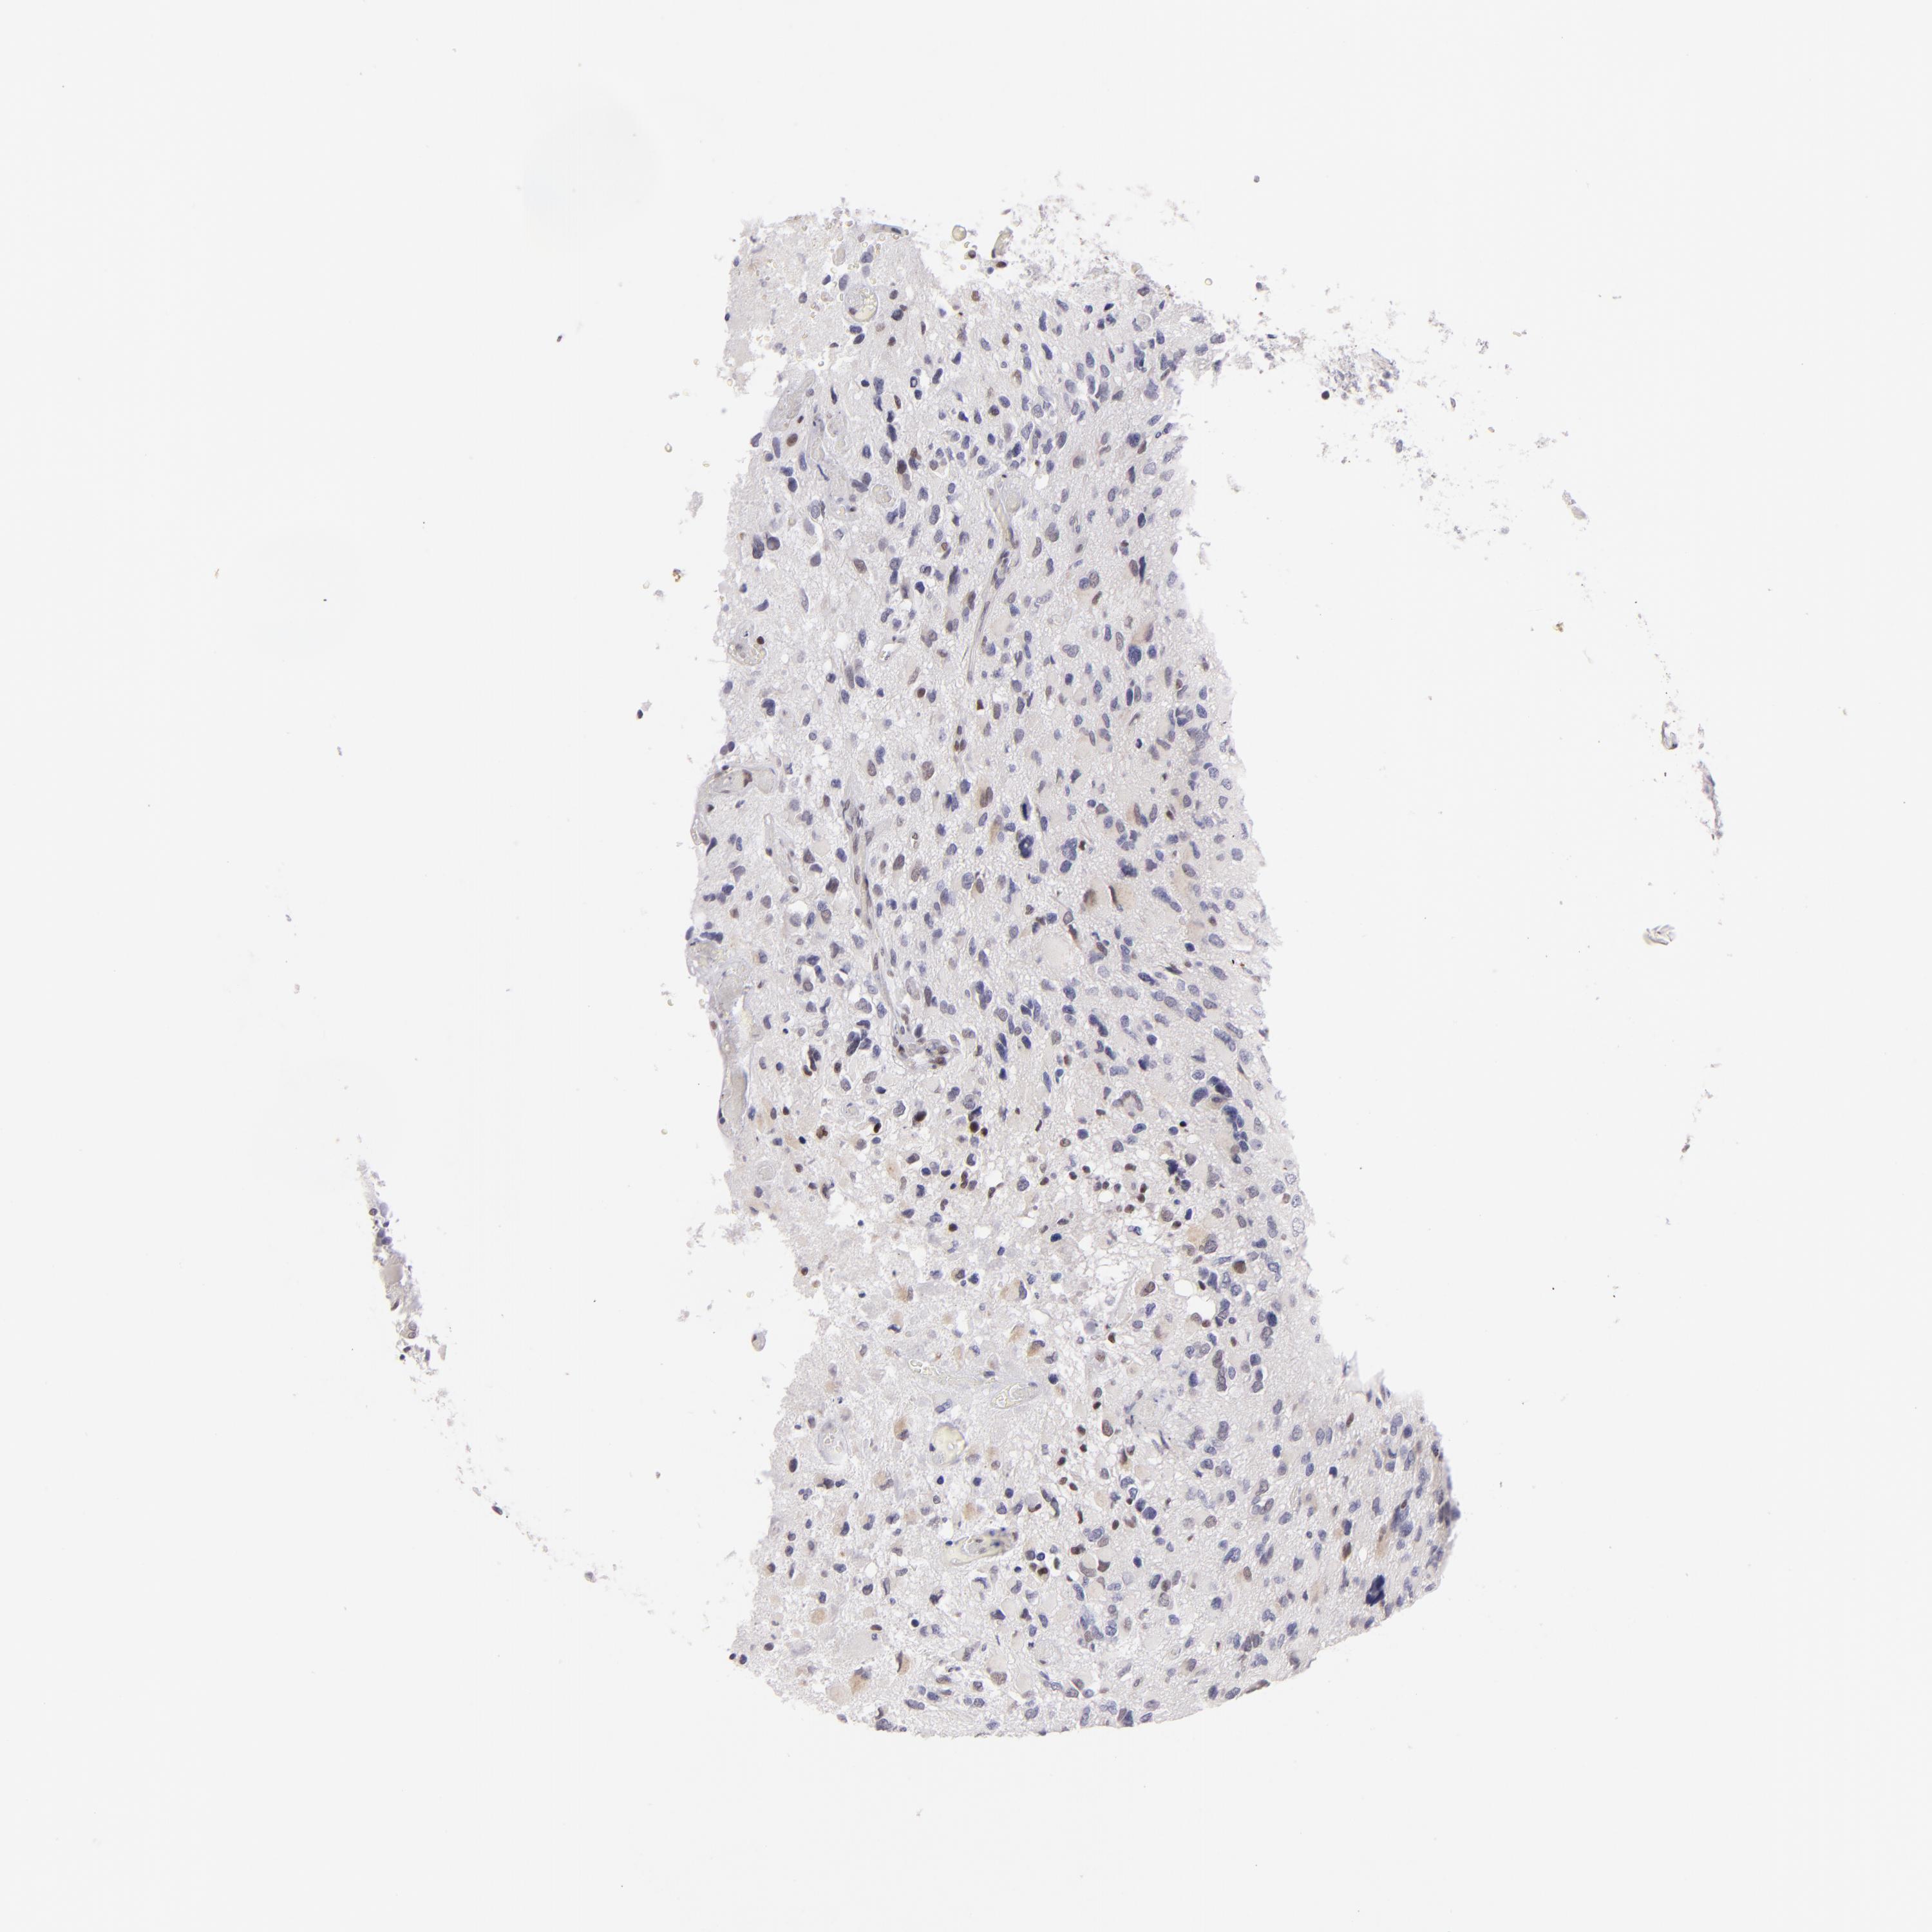

GLIOMA - Protein expressioni

A mouse-over function shows sample information and annotation data. Click on an image to view it in a full screen mode. Samples can be filtered based on level of antibody staining by selecting one or several of the following categories: high, medium, low and not detected. The assay and annotation is described here.

Note that samples used for immunohistochemistry by the Human Protein Atlas do not correspond to samples in the TCGA dataset.

Antibody stainingi

Antibody staining in the annotated cell types in the current human tissue is reported as not detected, low, medium, or high, based on conventional immunohistochemistry profiling in selected tissues. This score is based on the combination of the staining intensity and fraction of stained cells.

Each image is clickable and will lead to virtual microscopy that enables deeper exploration of all samples and also displays staining intensity scores, fraction scores and subcellular localization as well as patient and tissue information for each sample.

Antibody HPA064323

Antibody CAB002608

Staining

High

Medium

Low

Not detected

Intensity

Strong

Moderate

Weak

Negative

Quantity

>75%

75%-25%

<25%

None

Location

Nuclear

Cytoplasmic/membranous

Cytoplasmic/membranous,nuclear

Glioma, malignant, Low grade

Glioma, malignant, High grade